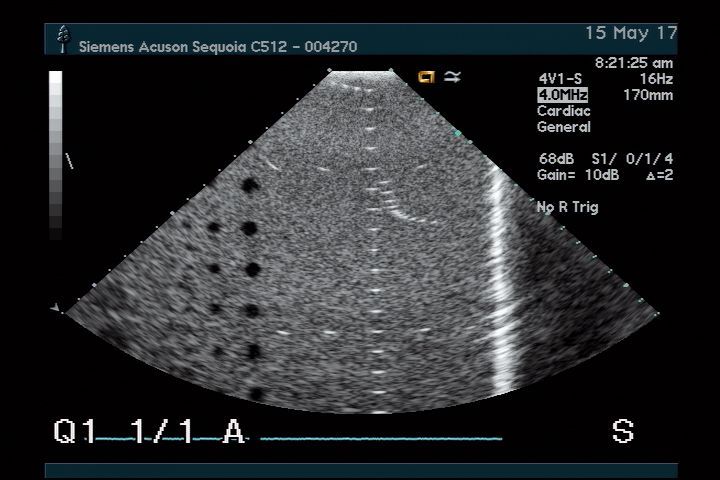

The Acuson 4V1 for Sequoia Ultrasound Transducer offers exceptional imaging capabilities. It provides clear, detailed images that are crucial for accurate diagnostics. Because of its advanced technology, this transducer is able to produce high-resolution images, so healthcare professionals can easily identify and assess various medical conditions. Furthermore, the ergonomic design of the Acuson 4V1 ensures comfort for both the patient and the clinician during examinations.

This transducer is not just limited to one type of examination; it is highly versatile and can be used for various applications in different clinical settings. Whether it’s for cardiac imaging, abdominal assessments, or vascular studies, the Acuson 4V1 meets the diverse needs of healthcare providers. Because it covers a wide range of frequencies, it allows for tailored imaging techniques, enhancing diagnostic accuracy. Thus, it becomes an essential tool in any medical facility.